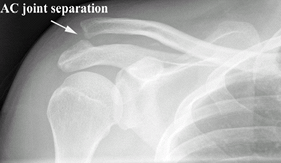

Fig. 2. Radiograph of an AC joint separation.

AC joint arthritis/AC separation (4):

Palpable point tenderness at the AC joint

Palpable step-off at the AC joint in the presence of a separation (Fig. 2)

Joint effusion may be present.